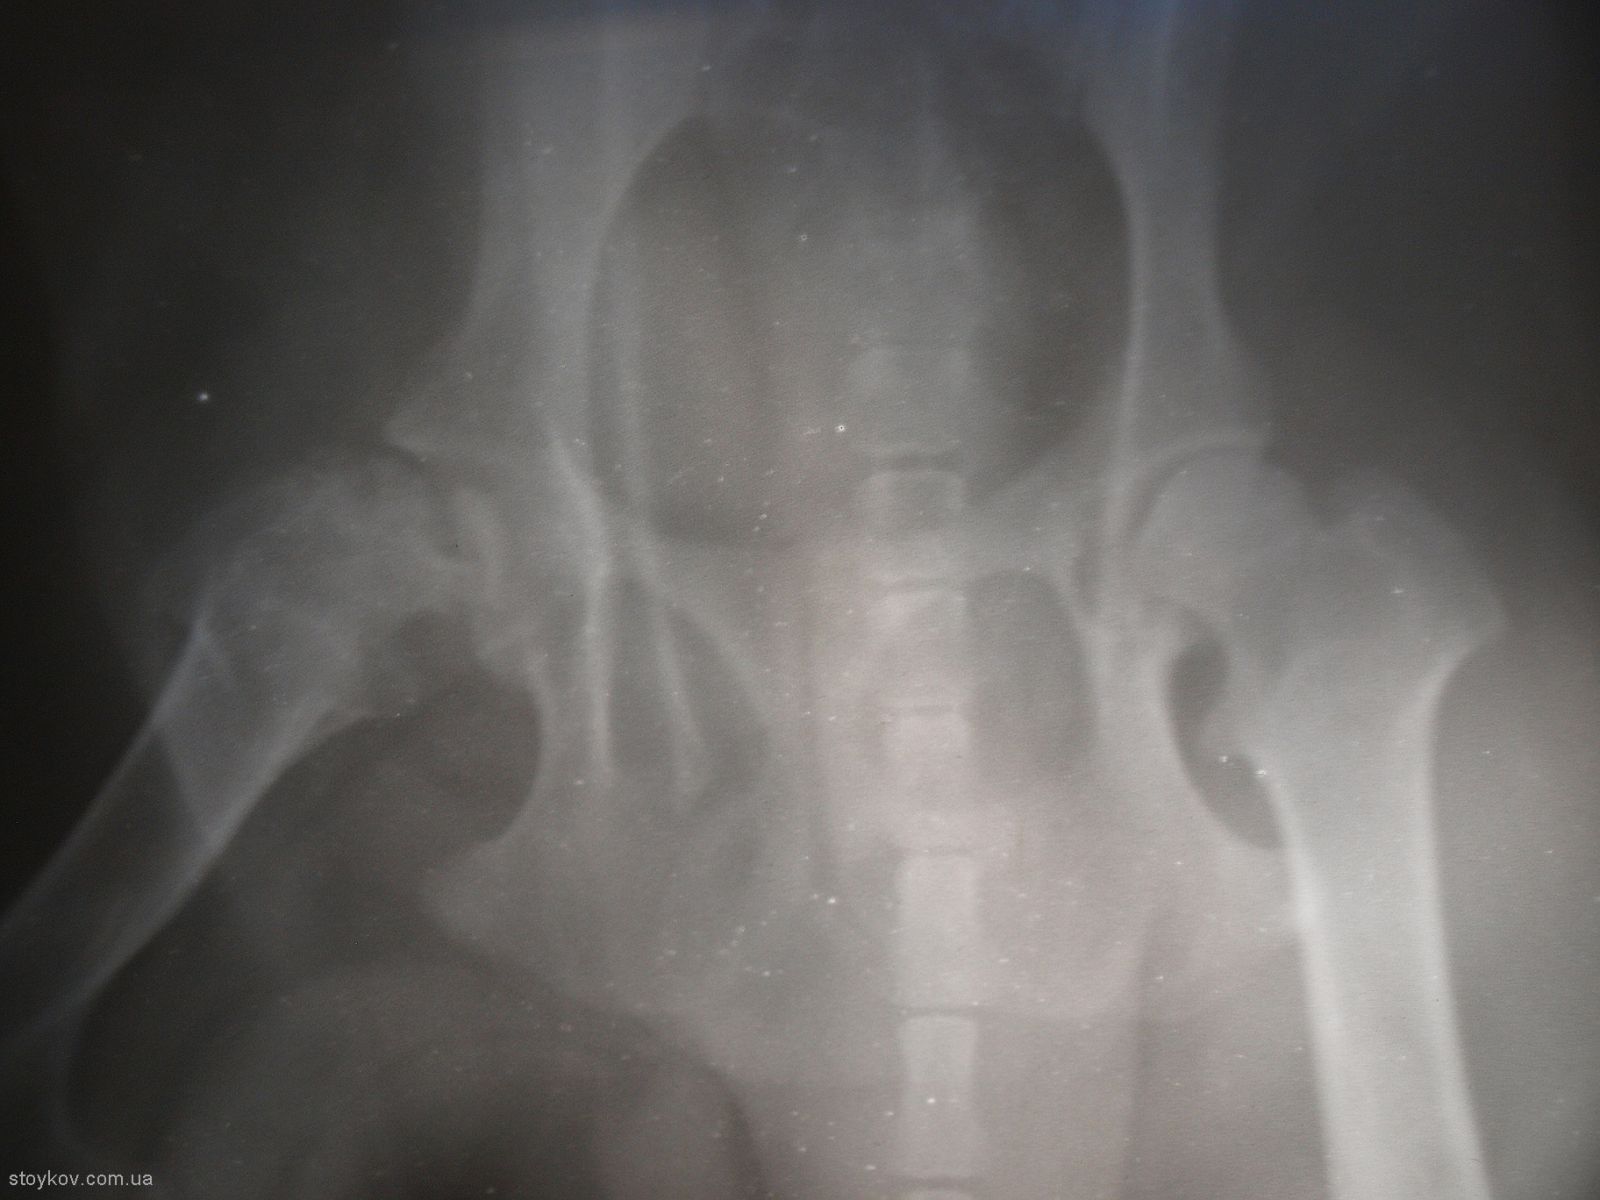

В перші місяці лікування проводиться консервативно. Важливо пам’ятати, що лікарські препарати практично не впливають на перебіг і подальший прогноз захворювання, тому основою консервативного періоду лікування повинно бути утримання тварини в маленькій клітці для іммобілізації кінцівки з метою зменшення зони ураження голівки стегна. Багато ветеринарних ортопедів вважають, що накладання пов’язки для іммобілізації може погіршити стан голівки стегнової кістки при гострому періоді хвороби LCP. Період консервативного лікування також є періодом спостереження, як етап для підтвердження діагнозу (порівняння рентгенівських знімків). Деякі тварини з діагнозом LCP після гострого перебігу хвороби починають опиратися на кінцівку і через півроку-рік функція частково відновлюється. Протягом подальшого життя тварина почувається відносно комфортно. Важливо відмітити, що у однієї тварини на рентгенівському знімку, що був зроблений через 3 роки голівка стегнової кістки була практично відсутня (як після резекції). То виникає запитання, чи варто мучити тварину півроку заради результату, якого можна досягти за два тижні?

Саме тому у більшості випадків вибір залишається за хірургічним лікуванням. Мета хірургічного лікування – зменшення болю, але зважаючи на невеликий розмір тварини, функція прооперованої кінцівки залишається задовільною. Для проведення операції потрібно використовувати остеотом або осциляторну пилку. Використання дротяної пилки не бажано тому, що у такому випадку зріз буде проведено у найвужчому місці шийки, тобто посередині, а потрібно відсікати всю шийку повністю. Не дивлячись на удавану простоту операції дуже важливо провести правильну лінію зрізу шийки стегна і максимально зберегти капсулу суглоба. Після відсікання шийки стегна потрібно ретельно зашити капсулу суглоба. Інколи, для збільшення прошарку м’яких тканин між стегновою кісткою і тазом, використовують техніку м’язового клаптику. Якщо така операція проводиться у собак до 7 кг маси тіла то інтерпозиція частини двоголового мускулу не обов’язкова.